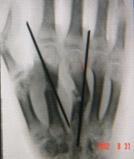

一種骨科常用的內固定材料,其原規格一般固定在二十公分左右,直徑在0.5-2毫米之間有不同的幾種規格。用於固定短小骨折或撕脫骨折等應力不大的骨折固定,也常被用在骨科手術中臨時骨折塊的固定中。由於廣泛套用,克氏針的最大直徑逐漸增加到4毫米隨著外固定支架的,配合外固定鎖釘來固定骨盆骨折、跟骨骨折等應急較大的骨折。

首先,按照諸位的方法可以用一枚克氏針固定骨折於解剖位置;然後,分別在骨折近端和遠端距骨折線0.5-1厘米處垂直於指骨縱軸鑽孔,過雙側骨皮質。此兩枚----直徑1.5mm克氏針應在一個平面內、且此平面應和指骨縱軸平行;最後,取出這兩枚克氏針,在針道處插入注射針頭作為導管,將1毫米的鋼絲穿過然後擰緊加壓-----相當於張力帶鋼絲,這樣的固定非常牢靠,術後可以早期鍛鍊,便於功能恢復。此方法還可用於指骨融合。